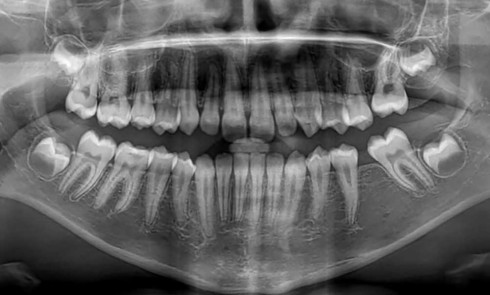

Quelles sont les 7 formes cliniques des épulis ? 1. Épulis inflammatoire (plasmocytaire) Nodule indolore, pédiculé, érythémateux, parfois ulcéré (fig. 1a)....